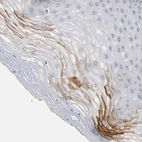

Immunohistochemical staining of human fallopian tube shows strong cytoplasmic granular positivity in glandular cells.